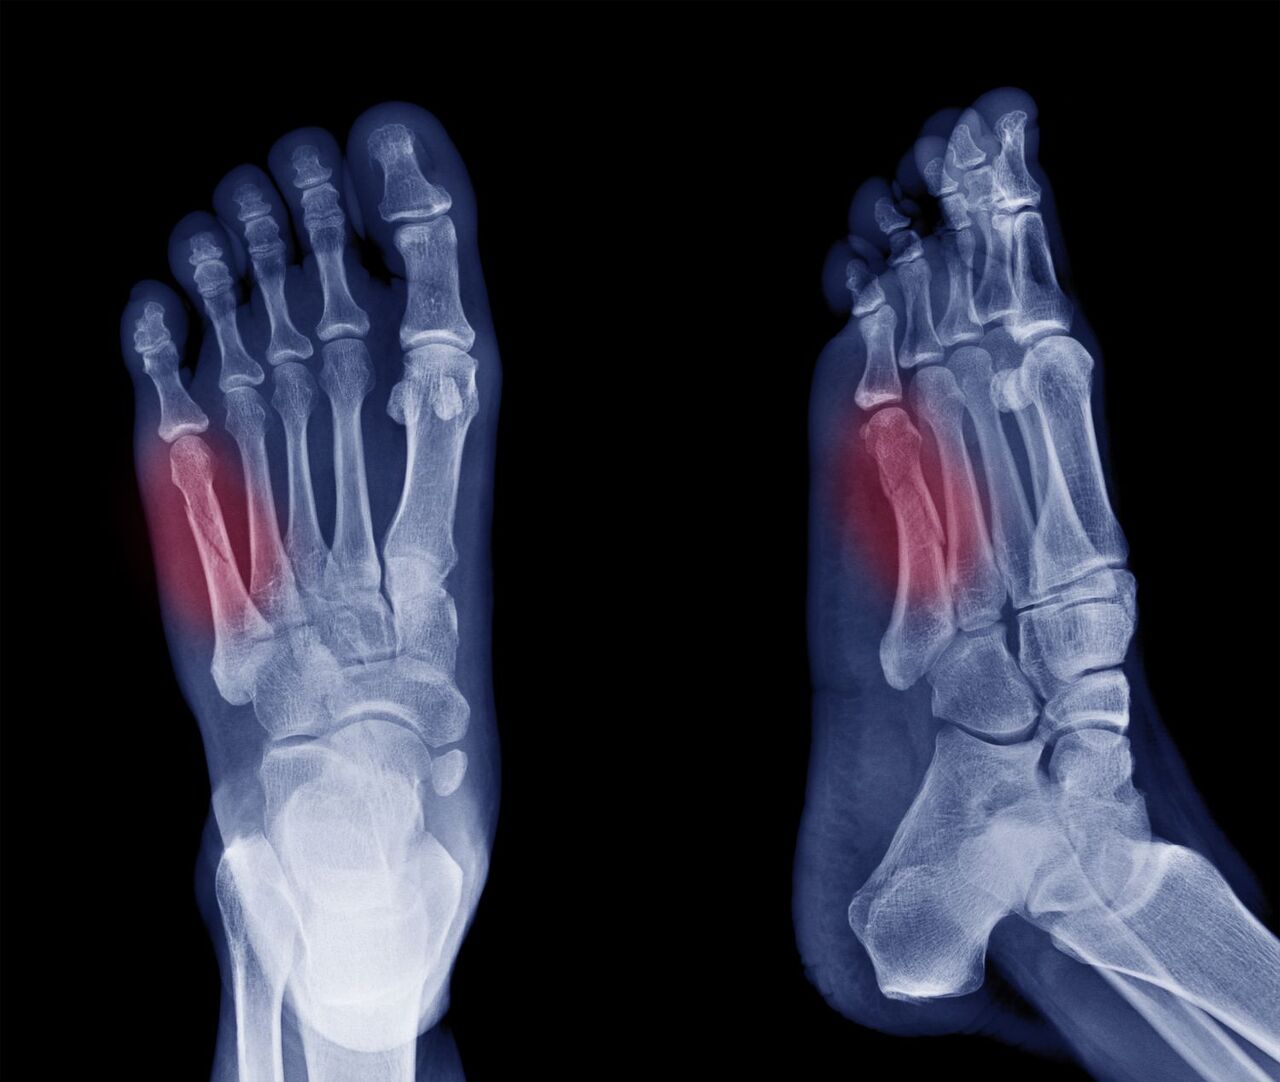

발가락 골절의 다양한 양상

발가락 골절은 흔히 발생하는 상황입니다. 이유는 다양하게 있을 수 있으며, 대표적으로는 실내에서 물건에 부딪히거나 높은 곳에서 떨어지는 등의 사고가 있습니다. 이 외에도 스포츠 활동 중 부상을 당하거나 교통사고 등에서도 발가락 골절이 발생할 수 있습니다. 발가락 골절은 크게 뼈가 완전히 부러진 경우와 뼈에 금만 간 경우로 나눌 수 있으며, 이에 따라 치료 방법과 기간이 다릅니다.